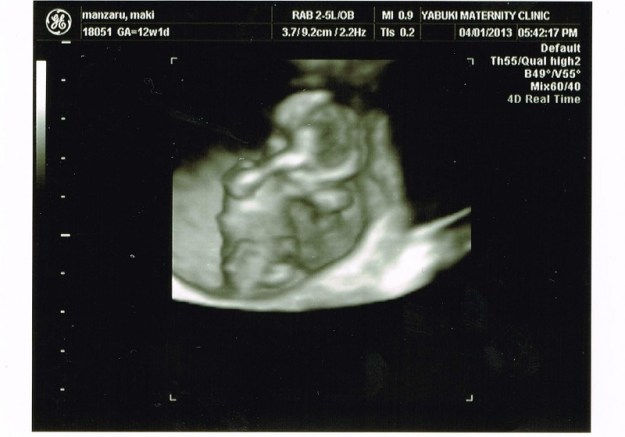

Coté foetus, c’est parfait, je touche du bois. Les echo sont maintenant en 3D, voir en 4D, et effectuées SUR le ventre, ce qui veut dire que je pourrais surement y assister la prochaine fois ! C’est du coup la première fois que l’on peut voir aussi clairement le foetus ! (remarquez que je ne sais pas quand il faut que j’abandonne le terme de « foetus » pour parler de « bébé » mais à la vue des echo, c’est maintenant plutot un bébé :x ).

ps : echo en 3D = photo en 3D, la 4D rajoute simplement la dimension de temps, ce qui veut dire qu’en fait c’est une vidéo.

Il est apparement très timide puisqu’il n’arrete pas de mettre son bras devant ses yeux !

12sa